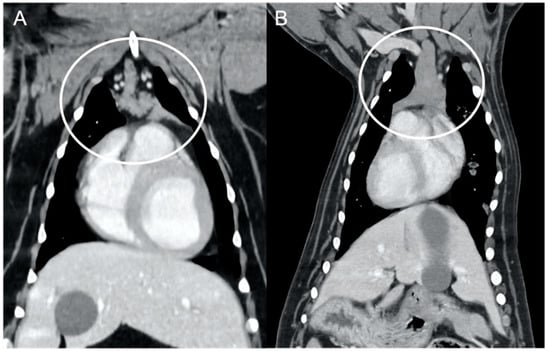

In both groups, most of the dogs presented with a triangular thymus (Figure 1); in the adult group, some dogs had an elongated thymus, and in the juvenile group, some dogs had a flattened thymus (Figure 2).

The overall appearance was lobulated in all of the adult dogs and homogeneous in all of the juvenile dogs (Figure 1 and Figure 3). The thymus was left-sided in all of the adult dogs, while it was located in the midline in a few juvenile dogs; one presented a thymus on the right side due to situs inversus (Figure 4). The maximum dimension of the thymus in the adult dogs group was always the length, while in some juvenile dogs, the maximum diameter was the width (Figure 2). The dimensions of the thymus were variable between different patients, with several breeds included and large differences in body weight between the dogs. For this reason, a ratio between the maximum diameter of the thymus (measured in cm) and the body weight (measured in kg) was calculated for each dog. The median ratio in the adult dogs group was 0.2 (minimum: 0.06; maximum: 0.4), while in juvenile dogs, it was 0.4 (minimum: 0.1; maximum: 1.4). The dogs with the higher ratio (>1) were in the juvenile group and they presented with spinal a cyst and enteritis and were 6 and 7 months old, respectively. The dogs with the lower ratio (<0.1) were in the adult group and they presented with muscular hemangiosarcoma (one dog) and synovial cell sarcoma (two dogs) and were 2, 6, and 8 years old, respectively.

Figure 1. Shape of the thymus (circled) in an adult dog (A) compared to a young dog (B). Post-contrast dorsal CT reconstruction. Note the different relative sizes of the thymus in the two dogs, and the heterogeneous (lobulated) appearance of the thymus in (A) with respect to the thymus in (B). In both cases, the shape of the thymus is triangular.